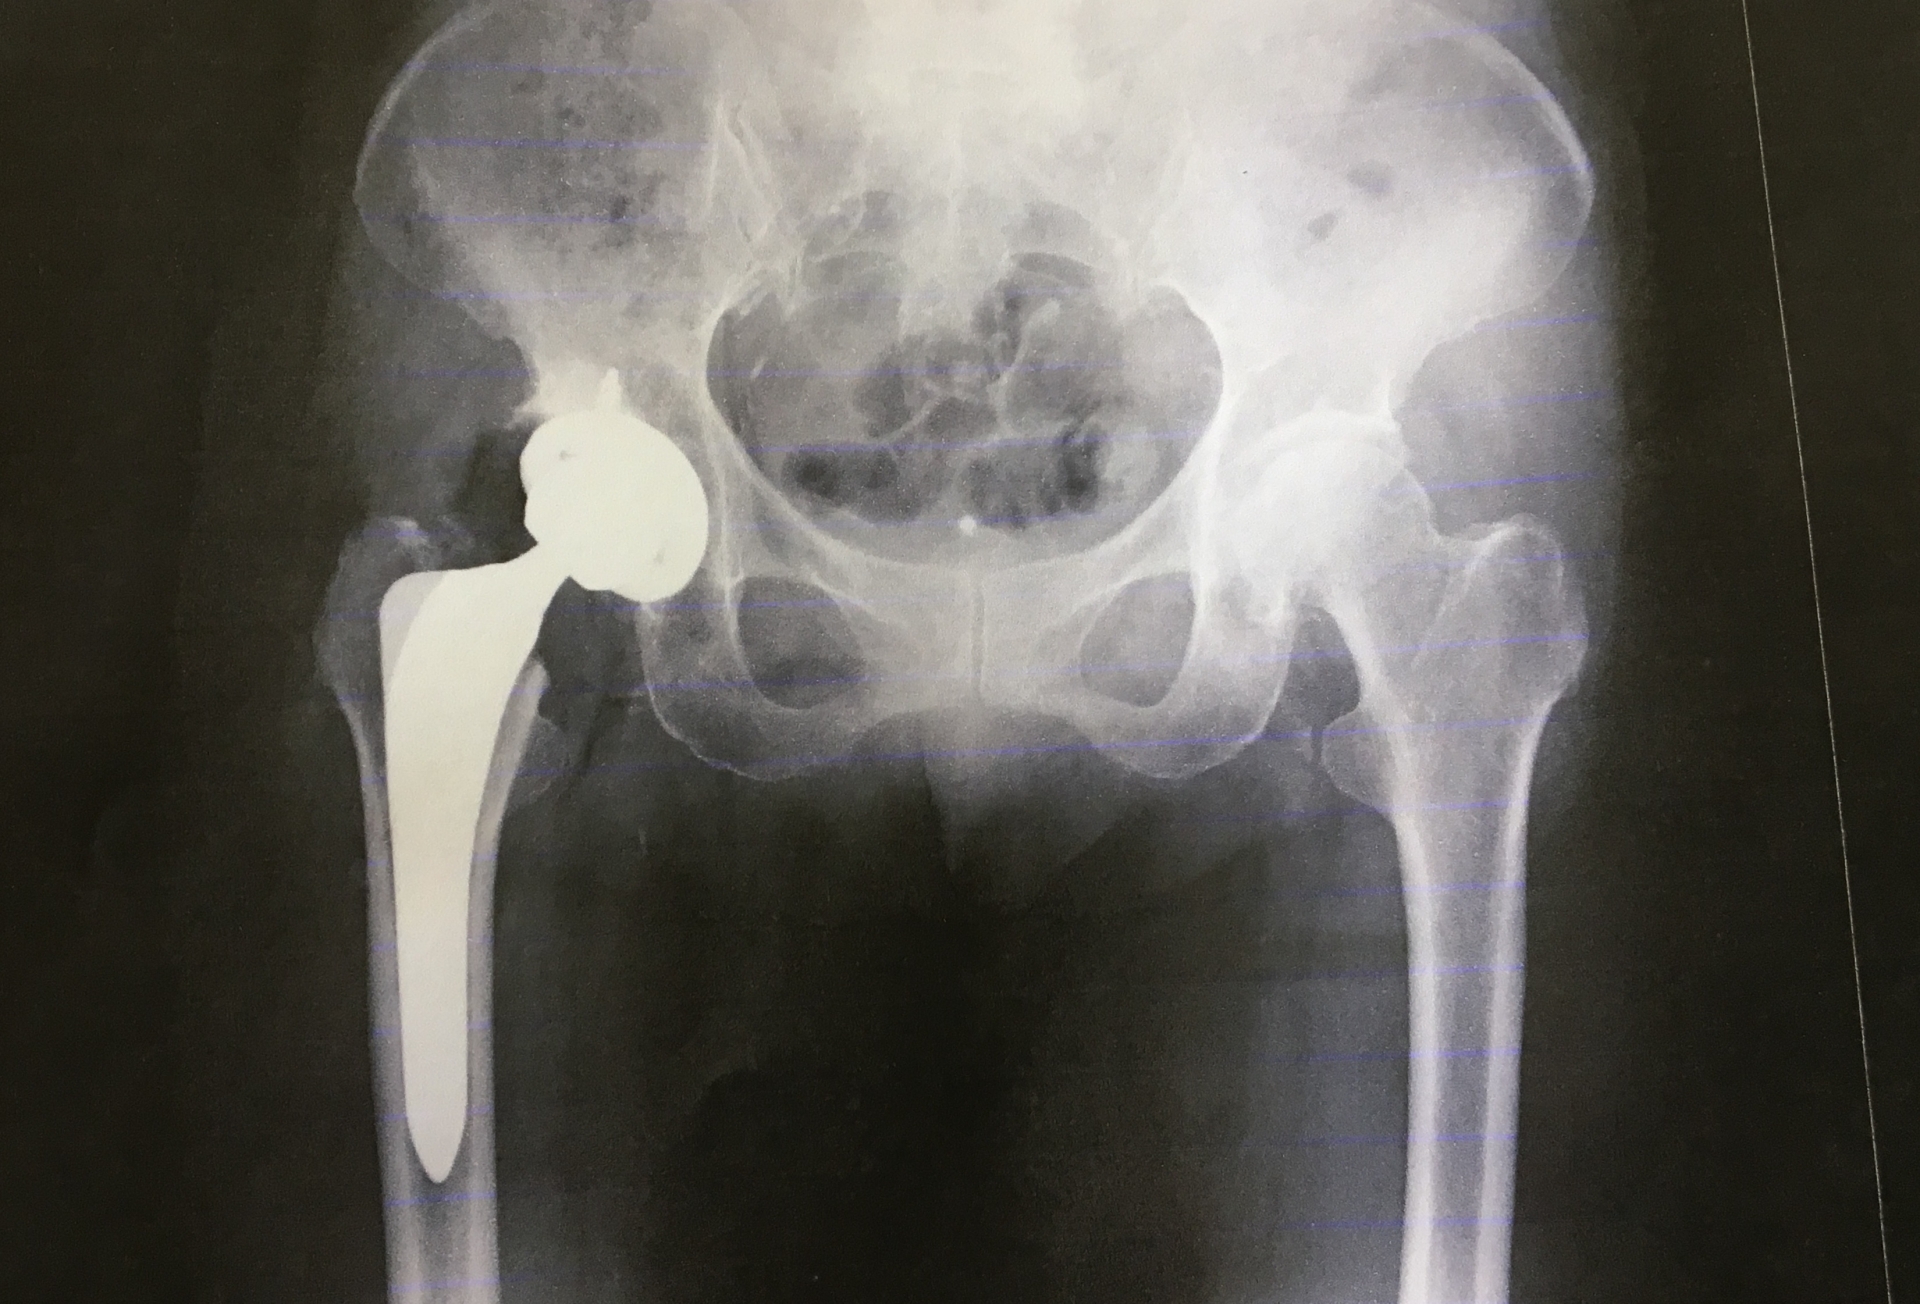

人工股関節全置換術

この手術では、外科医は大腿骨頭とソケットを含む股関節全体を交換します。その代わりに、外科医は金属、プラスチック、またはセラミックで作られた人工コンポーネントを取り付けます。

それぞれの手術選択肢には利点とリスクが伴います。医師は、最適な治療法を決定する前に、利用可能な選択肢を患者に案内します。